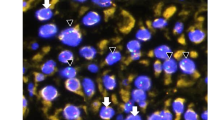

In order to determine whether the SDHAF2 gene is expressed in parathyroid tissue, total RNA was isolated from snap-frozen normal parathyroid cells and adrenal medulla (control). Reverse-transcriptase PCR of the cDNA revealed the expected size fragment in cDNA from normal parathyroid tissue and adrenal medulla (Fig. 1a), and verified by automated sequencing. Additionally, we demonstrated SDHAF2 gene expression in another cohort of 14 sporadic parathyroid adenomas from patients with PHPT and three normal parathyroid tissues (Fig. 1b).

a The novel endocrine tumor suppressor gene, SDHAF2, is expressed in parathyroid cells. Total RNA (10 μg) was isolated from snap-frozen parathyroid tissue and adrenal medulla (control). The expected product is visualized on a 1% agarose gel. Lanes 1 and 8, marker; lane 2, reverse transcriptase; lane 3, cDNA from normal parathyroid cells; lane 4, negative control (H20); lane 5, reverse transcriptase; lane 6, cDNA from adrenal medulla; and lane 7, negative control (H20). b. The novel endocrine tumor suppressor gene, SDHAF2, is expressed in parathyroid cells. Total RNA (10 μg) was isolated from snap-frozen parathyroid tissue both diseased and normal. The expected product is visualized on a 1% agarose gel. Lanes 1 through 14 represent parathyroid Adenomas, and lanes 15–17 are normal parathyroid tissue. Lanes marked “L” denote the DNA Ladder and the “N” is the negative control lane